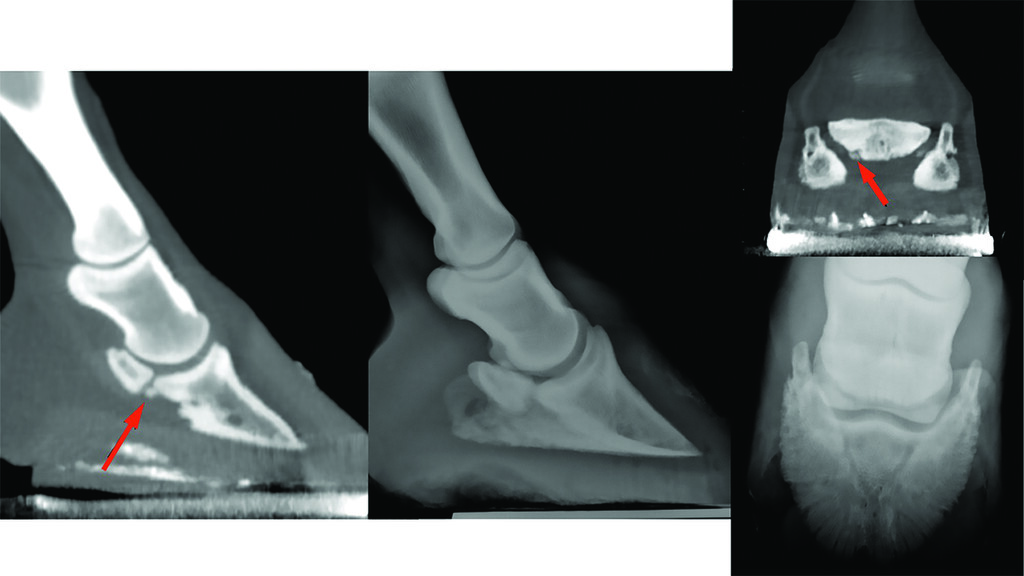

Sabrina Brounts, DVM, PhD, DACVS, DACVSMR, from the Department of Surgical Sciences, School of Veterinary Medicine at the University of Wisconsin, Madison, and colleagues recently studied a helical fan-beam computed tomography (CT) system’s ability to diagnose distal limb issues in standing, sedated horses (2022).

In their study, Brounts et al. used the equine unit from AstoCT to scan the distal limbs of 167 standing, sedated lame horses in a two-year period. It has the ability to scan both limbs simultaneously in a natural weight-bearing position with short acquisition time.

Brounts’ team obtained diagnostic scans from all study horses and localized lameness to the foot or pastern in 53% of cases. Almost half of those horses were diagnosed with navicular disease. Other causes of foot pain in the study included foot abscess, fracture of the distal phalanx, keratoma, osteoarthritis, pedal osteitis, fracture of the middle phalanx or navicular bone, and septic tendon sheath.

“Standing CT and PET/CT imaging might be the future for podotrochlosis horses, especially because these are imaging modalities that are becoming more and more available standing in equine practice,” says Brounts. “If you suspect a horse with navicular syndrome or a foot problem based on your clinical examination, and your radiographs do not show/confirm that diagnosis, I recommend a CT scan of that horse. These days when we have a horse that is foot-sore, we do not take radiographs anymore, we go straight to CT scanning because it will give us more information/detail and more dimensions to evaluate that foot, including the navicular apparatus.”